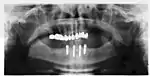

The long-term success of implants is determined, in part, by the forces they have to support. As implants have no periodontal ligament, there is no sensation of pressure when biting so the forces created are higher. To offset this, the location of implants must distribute forces evenly across the prosthetics they support.[28]: 15–39 Concentrated forces can result in fracture of the bridgework, implant components, or loss of bone adjacent the implant.[29] The ultimate location of implants is based on both biologic (bone type, vital structures, health) and mechanical factors. Implants placed in thicker, stronger bone like that found in the front part of the bottom jaw have lower failure rates than implants placed in lower density bone, such as the back part of the upper jaw. People who grind their teeth also increase the force on implants and increase the likelihood of failures.[15]: 201–208

When a more exacting plan is needed beyond clinical judgment, the dentist will make an acrylic guide (called a stent) prior to surgery which guides optimal positioning of the implant. Increasingly, dentists opt to get a CT scan of the jaws and any existing dentures, then plan the surgery on CAD/CAM software. The stent can then be made using stereolithography following computerized planning of a case from the CT scan. The use of CT scanning in complex cases also helps the surgeon identify and avoid vital structures such as the inferior alveolar nerve and the sinus.[31][32]: 1199